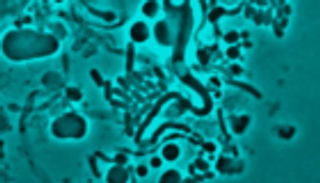

وطور العلماء مادة يمكنها تقييم البيئات الدقيقة، ثم دمجوا المادة التي وضعوها في الضمادات، واختبروها على الجروح في الفئران، وكانت الفئران مصابة ببكتريا "إي كولاي" الحساسة للعقاقير.

وخلال الاختبار، تغيرت الضمادة من الأخضر إلى الأصفر، وأطلقت مضادا حيويا لقتل الميكروبات، وعندما كانت البكتيريا المقاومة للعقاقير موجودة تحولت الضمادة إلى اللون الأحمر، بعد ملامستها لإنزيم ينتج عن الميكروبات المقاومة.